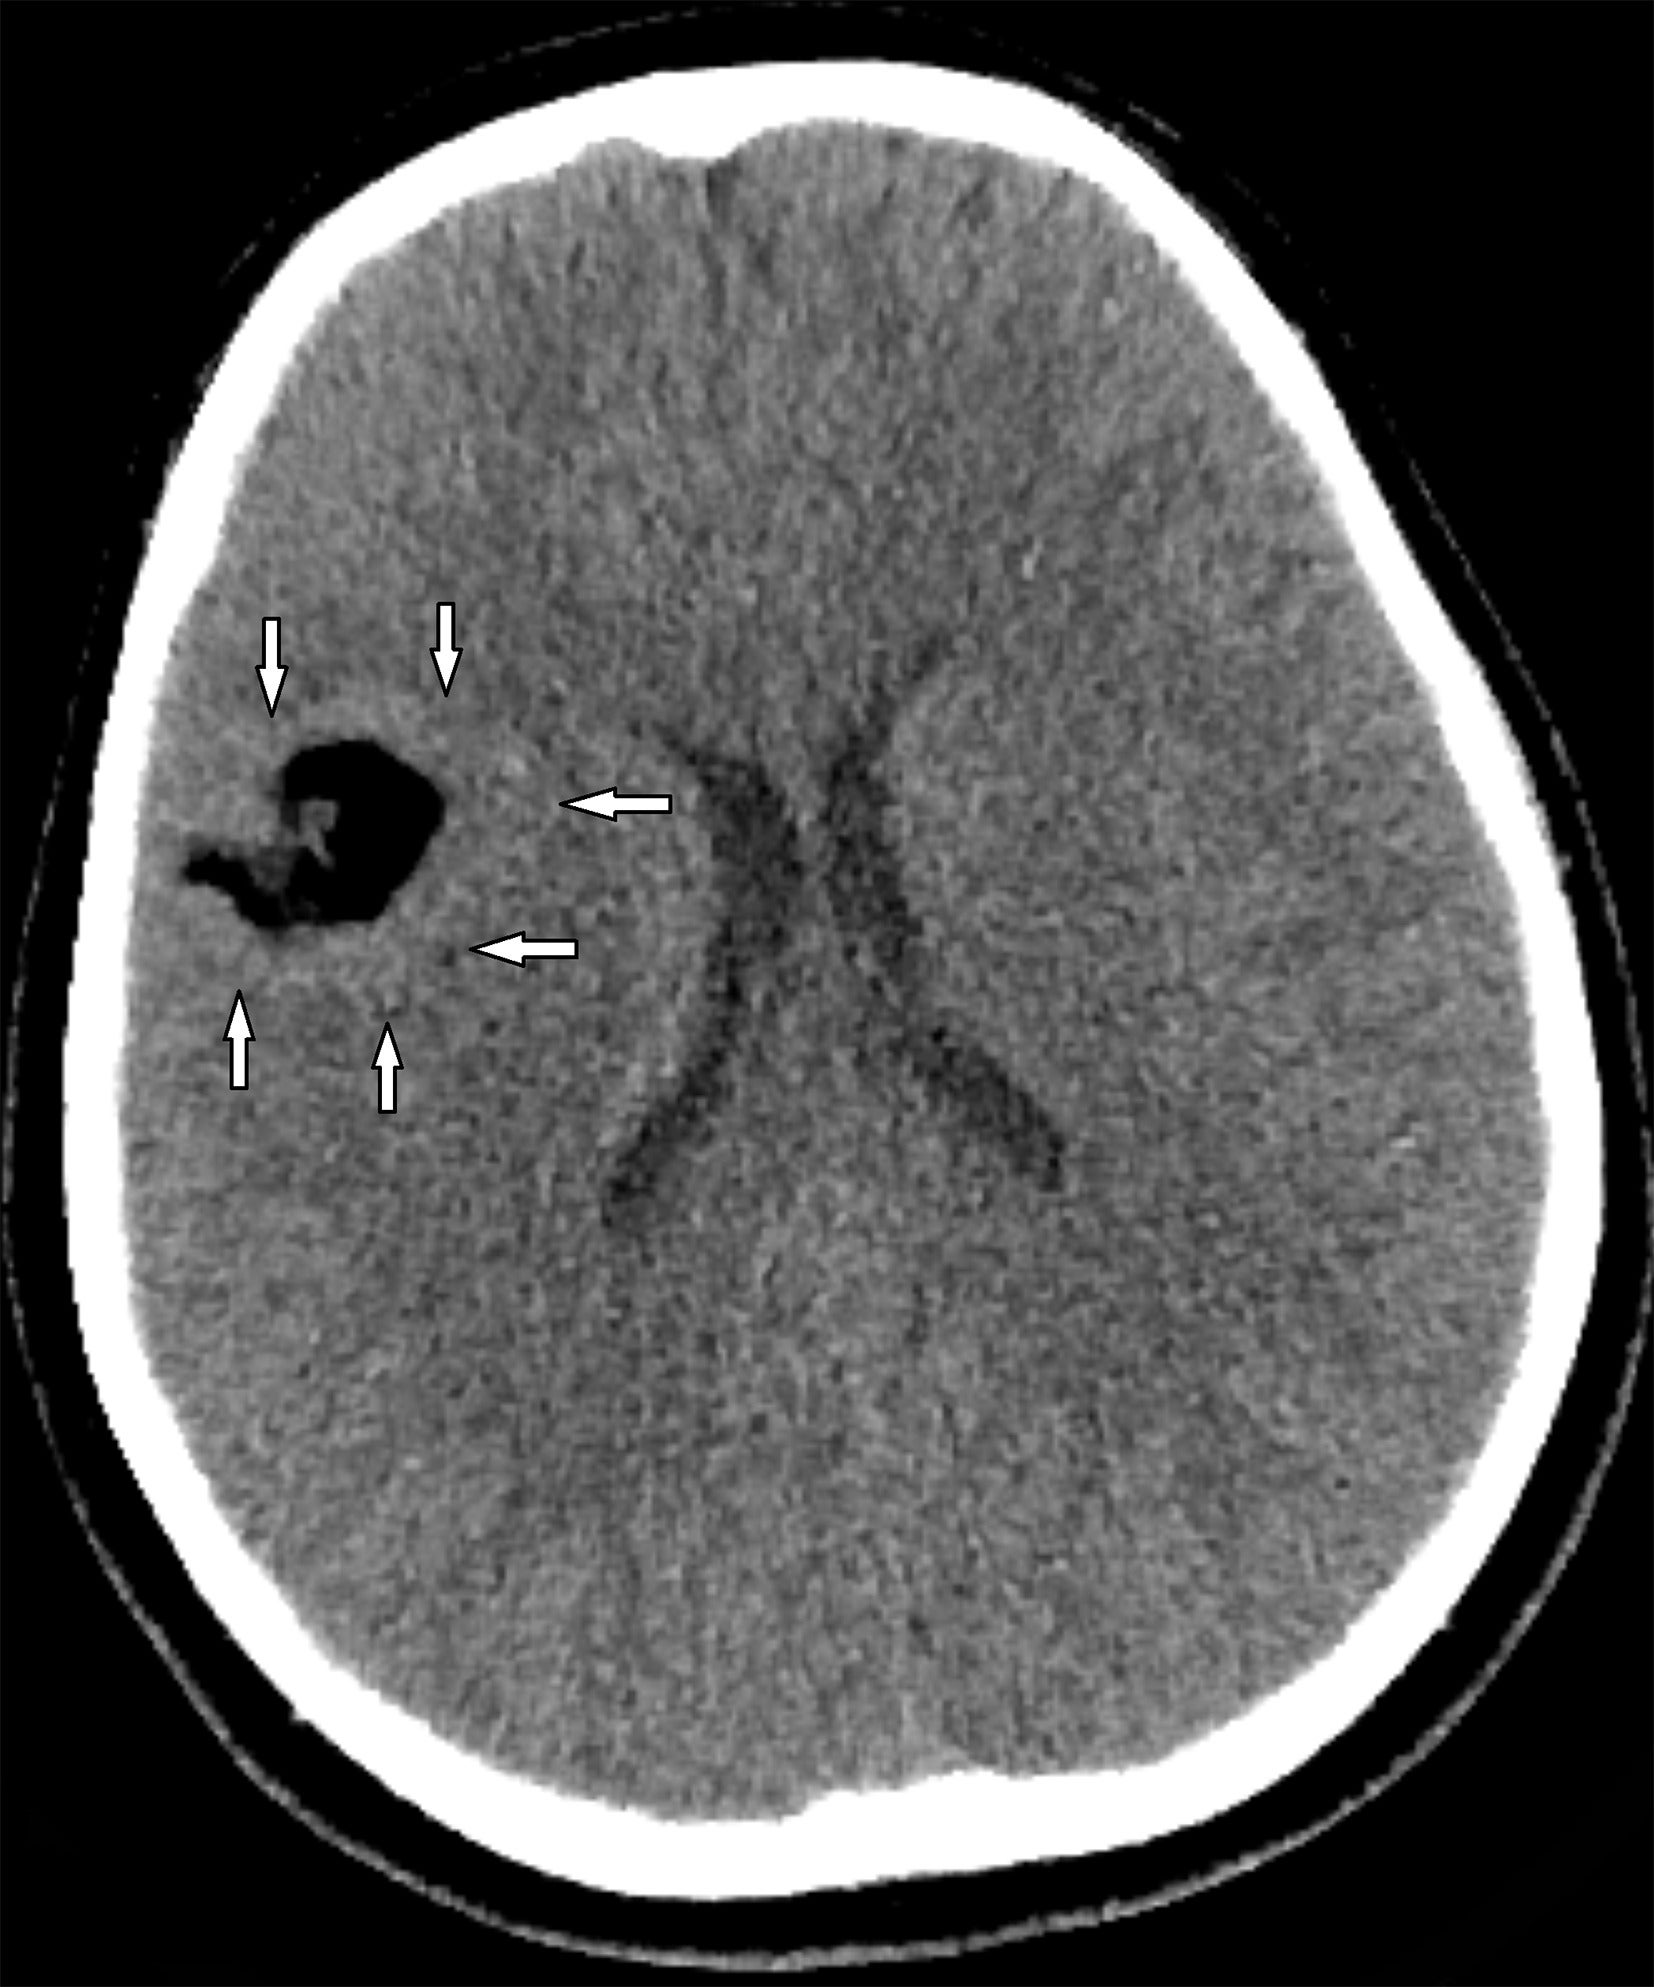

Head CT ( Figure 1 ) revealed a fat-attenuation lobulated mass overlying the right Sylvian fissure, surrounded by abnormally thick underlying cortex. Brain MRI ( Figure 2 ) demonstrated a well-defined lobulated extra-axial right Sylvian fissure mass with high signal intensity in T1 and T2, surrounded by chemical shift artifact. The lesion was encased by a gray matter-lined cortical cleft. The signal dropped out in fat saturation sequences. No enhancement was noted except for the venous component traversing through the lesion.

Axial CT image demonstrates a well-defined extra-axial mass of fat attenuation with lobulated margins centered in the right Sylvian fissure. The surrounding cortex appears abnormally thickened (arrows).